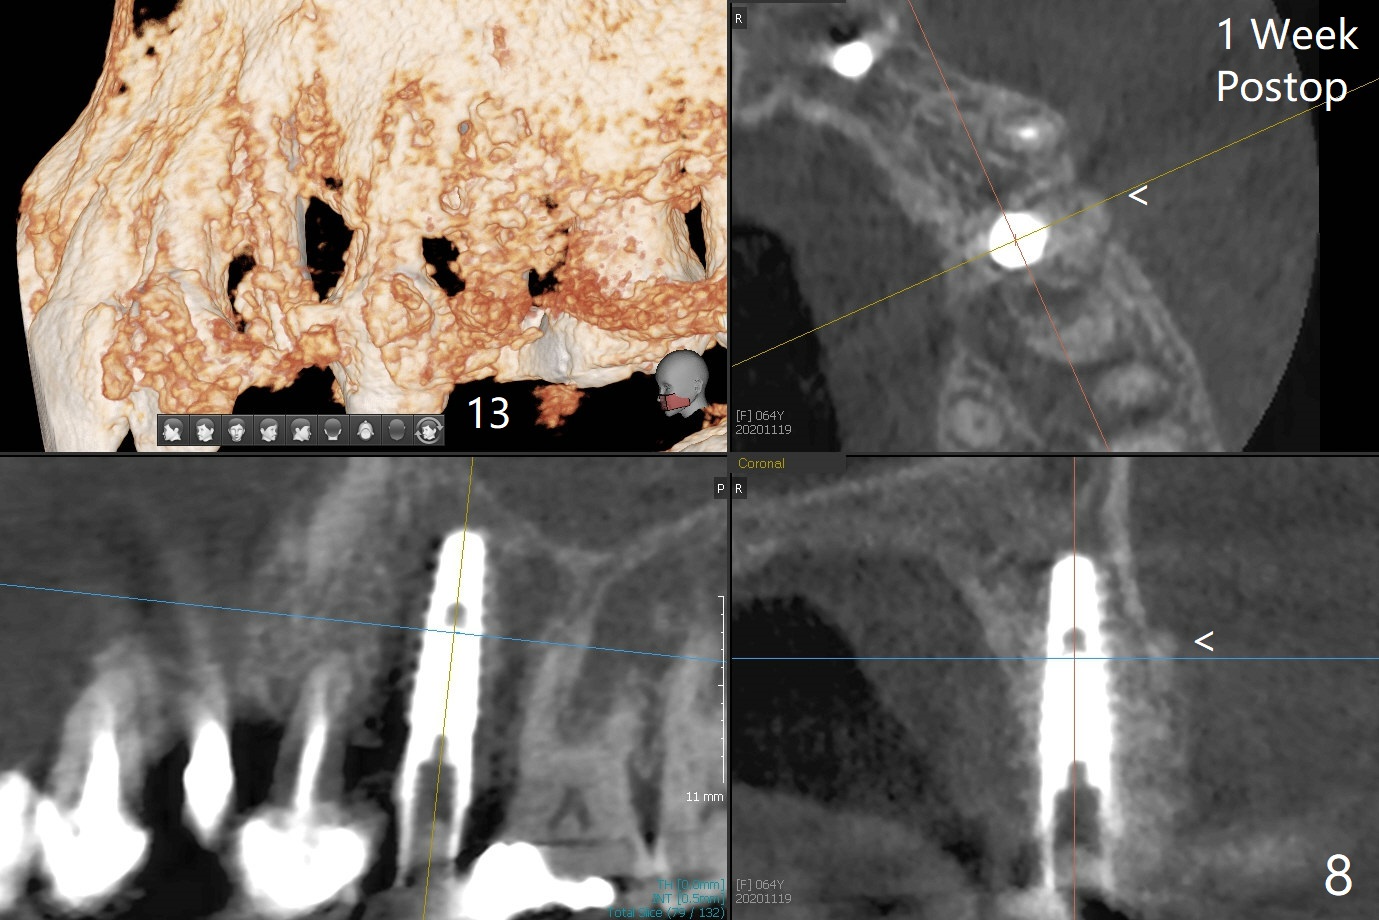

害怕病人局麻药很慢起效,术中身体会动,术中决定减小右下6,7植体直径0.5毫米(与导板设计相比),一旦植体越过牙槽嵴顶骨皮质,稳定性突然减低(图一)。尽管扭力10-15Ncm,为了避免二期手术,放置愈合基台(图二),6基台没有就位(箭头),因为植体种太深了,牙槽骨阻挡(*)基台就位。当取出6基台时,植体一起旋出,重新植入时,就没有种那么深(图三:箭头,与图一,二对比)。由于扭力低,只好放置愈合帽,骨粉(*),GEM Cap(6-9月胶原膜)和牙周胶水。由于导板设计缘故,左上5拔除,种植后,才开始左上3一段式植体植入(图四),5也植入太深(图五),必须放置最小直径最长袖(cuff)的基台(图六),今后导板即刻植牙先不要到达设计深度。术后一周CT显示尖牙植体位于牙槽骨内(图七 (>:腭侧牙槽嵴))。Bone graft fills in the buccal apical defect at #13 one week postop (Fig.8 <). 术后两个月左上3临时牙冠折裂,5松动(图九,十),后者取出衬里,软组织愈合。术后8个月左上3,5取模,右下6 uncover,愈合帽表面覆盖骨质,把7号牙愈合基台放到6号牙上,而7号牙放置4.5x4(4)毫米修复基台,固定牙周敷料,这样6号牙伤口不必缝合。术后8.5个月右下6放置4.5x7.5(4)毫米基台,发现7基台没有就位(图十一:箭头),通过旋转7 基台,终于就位(图十二),螺丝往下移位(与图十一:横线对比),但是基台边缘太低,不利于取模。改用5.5x4(5)毫米UF基台,临床上不能就位,局麻使用5.5毫米Profile Drill后,才能就位(图十三),螺丝下端超越最低螺沟(横线)。